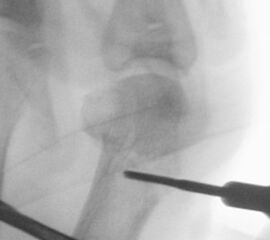

• Positionierung des Bildwandlers: 90° Winkel zum Os metatarsale I. Benötigt wird die Durchleuchtung des Vorfußes a.p., seitlich und schräg.

Operationstechnik

Der von Isham/Reverdin beschriebenen minimal invasiven Technik zur Korrektur einer Hallux valgus Deformität liegen 4 Operationsschritte zu Grunde:

1. Abtragung der Exostose am Köpfchen des 1. Mittelfußknochens

2. Subcapitale intraartikuläre Osteotomie

3. Laterales Release

4. Akin Osteotomie der Großzehengrundphalanx

Die Folge der Operationsschritte sollte strikt von 1. - 4. erfolgen, da ansonsten die mediale Closing Wedge Osteotomie bei vorzeitigem lateralem Release und/oder Akin Osteotomie nicht geschlossen werden kann. Nach der von Isham beschriebenen Originaltechnik finden Implantate keine Anwendung, zur Sicherung und besseren Fixation können osteosynthetische Verfahren angewandt werden (siehe auch Fehler, Gefahren und Komplikationen).